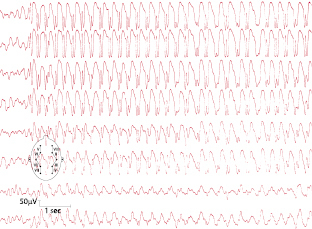

Der Erkrankungsgipfel liegt zwischen dem 5. und 9. Lebensjahr. Kennzeichnend ist das täglich gehäufte Auftreten von Absencen. Die Prognose ist günstig. Bei etwa 30% der Patienten können jedoch im Verlauf tonisch-klonische Anfälle hinzutreten. Abzugrenzen ist die frühkindliche und juvenile Absenceepilepsie. Das EEG zeigt während einer Absence generalisierte bilateral-synchrone, regelmäßige 3/s „spike-waves“ (Abb. 7.2).